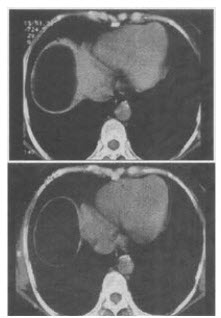

患者男,30岁,右下腹稍隆起,CT检查如图,最可能的诊断为()。

A、右膈下脓肿

B、间位结肠

C、右膈下脂肪瘤

D、右下肺肺大疱

E、右下肺炎

C